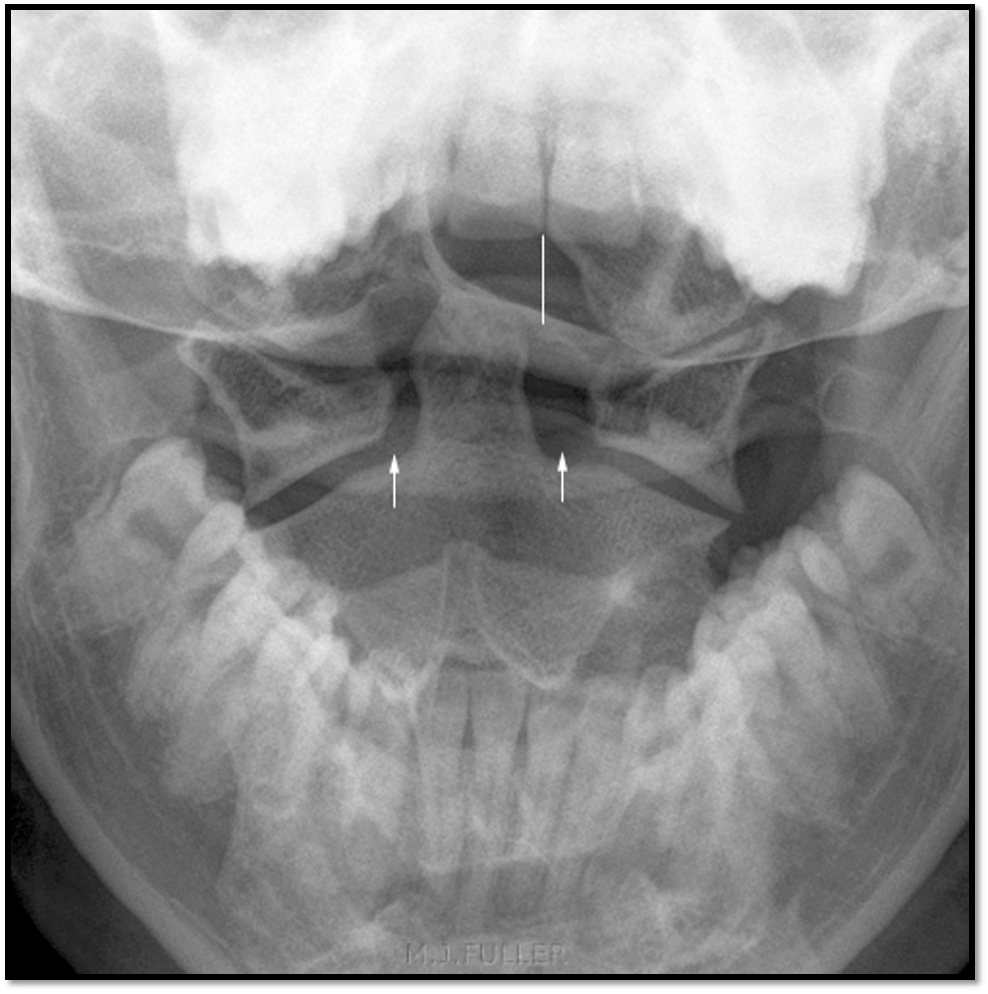

17

Q

A

• need to tuck chin

• nose is slightly rotated to the right